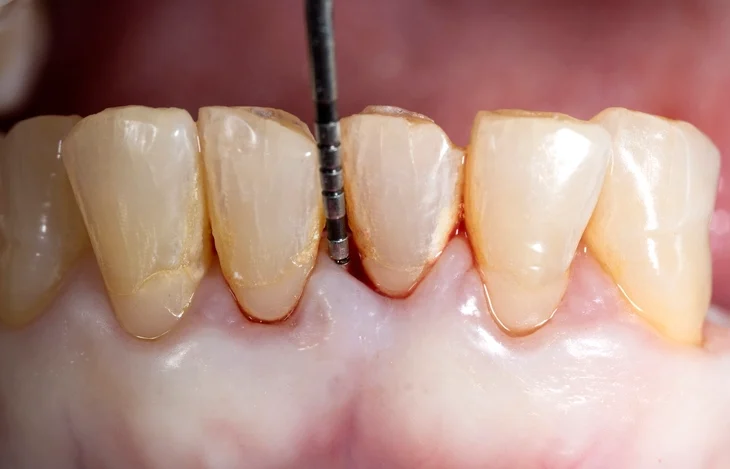

Periodontal Probing

Probing Pocket Depth (PPD)

Probing depth is measured from the gingival margin to the base of the pocket. It reflects current inflammatory status rather than the true historical loss of attachment.

However, in the presence of gingival enlargement, probing depth may overestimate the severity of attachment loss, while in cases of gingival recession, it may underestimate it.

Clinical Attachment Level (CAL)

The Clinical Attachment Level provides a more accurate measure of periodontal destruction, as it is measured from a fixed point—the cementoenamel junction—to the base of the pocket.

CAL = Pocket Depth + Recession (if present).

This measure allows comparison between visits and is essential for monitoring disease progression or healing following therapy.

Probes and Technique

A periodontal probe is the principal instrument for detecting pockets. The WHO probe, used for the Basic Periodontal Examination (BPE), has a 0.5mm ball tip and a black band between 3.5mm and 5.5mm to aid visualization.

Probing Variables:

- Tissue Tone: Edematous tissues allow deeper penetration.

- Force Applied: Should be approximately 20–25g to prevent trauma.

- Probe Design: Diameter and calibration markings affect readings.

Inflamed tissue offers less resistance, and probes may penetrate beyond the junctional epithelium, leading to overestimation. Therefore, the term probing pocket depth is preferred to simply pocket depth.